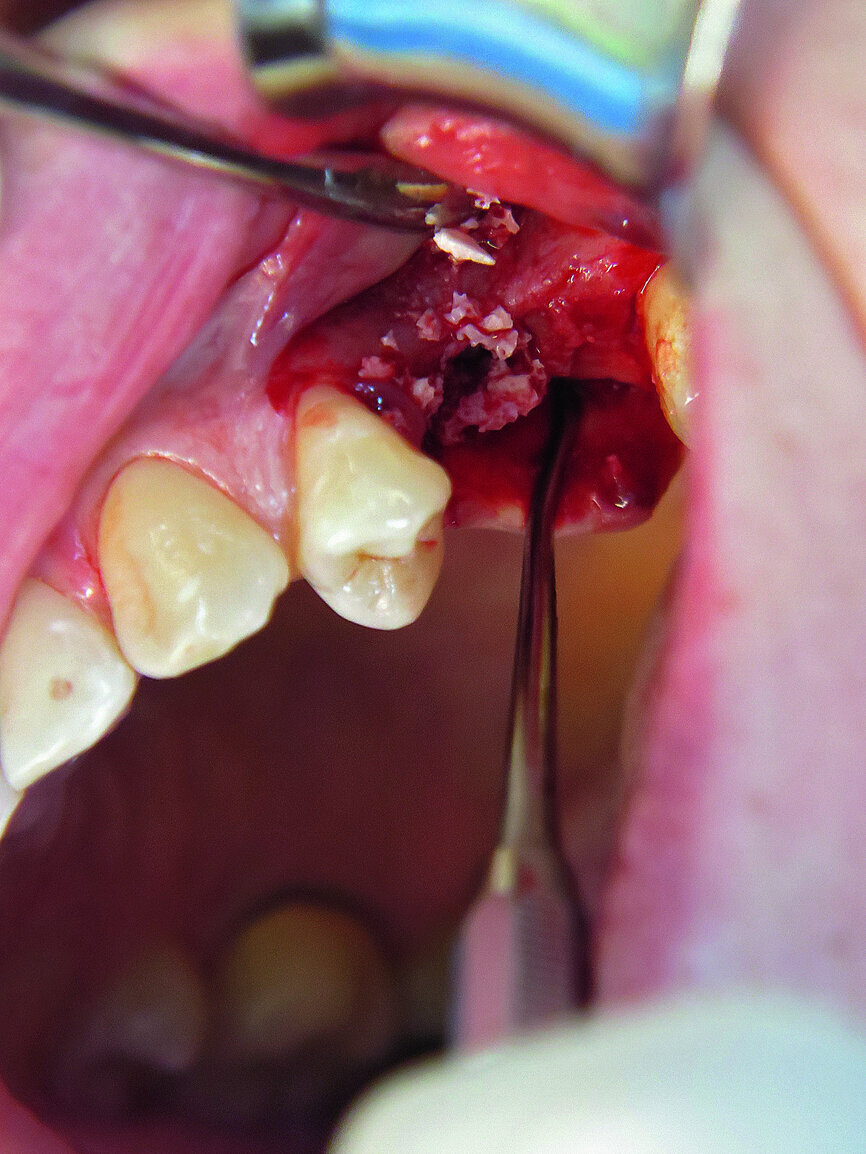

Fig. 10: 3-D augmentation using NanoBone.

The first was a 51-year-old patient who smoked 30 cigarettes per day and suffered from diabetes and stress (Figs. 1–8). The second was a 76-year-old male patient in good physical condition who smoked 40 cigarettes per day. He underwent reconstruction of the premaxilla (Figs. 9–13). The third was a healthy female patient of 24 years of age who smoked 20 cigarettes per day. She required a sinus lift in region #25 (Figs. 14–21). The patients were informed of the intended process in detail and signed the surgical protocol containing information concerning possible risks of failure and complications, as well as information on the alloplastic and synthetic materials to be used.

In our cases NanoBone, pericard membrane (imperiOs) and autologous bone chips were used for augmentation. NanoBone is an efficient nano-structure nano-crystalline hydroxyapatite embedded in a highly porous silica gel matrix. NanoBone is a safe product and stimulates the formation of collagen and bone. As an effect, many osteoblasts are seen in the early stage of regeneration. NanoBone has been on the market three years in the form of putty. NanoBone putty has a high consistency and is optimal for use to rebuild vertical bone. In general, no additional membranes are necessary. Its special structure results in rapid bone formation. As the osteoclasts resorb the granules, NanoBone is completely substituted by bone and no foreign substances will influence natural biomechanics.

Alternatively, NanoBone block material is now on the market and is a safe and rapid solution for block augmentation. Animal studies have shown that it induces quick bone formation. It offers an alternative to autogenous bone blocks for improving the implant bed in the case of vertical and horizontal bone deficits. In two patients with defects of the lower jaw, NanoBone block was used to optimise horizontal defects. NanoBone material was fixed with CAMLOG screws and a collagen membrane was used (RESORBA Medical).